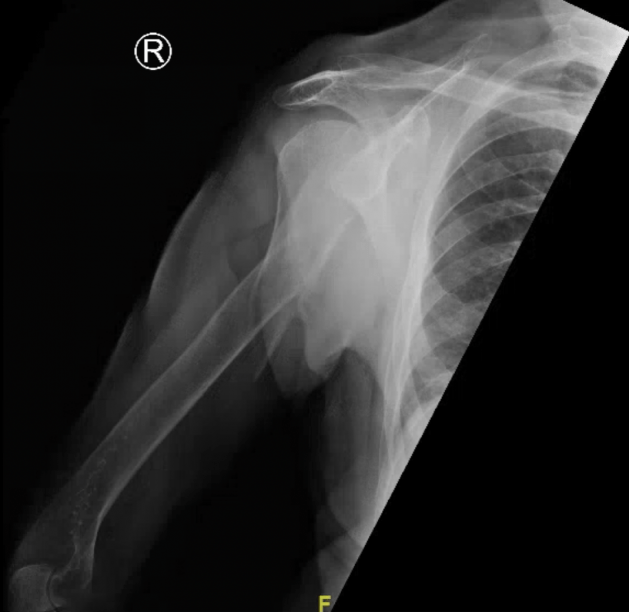

What’s the Diagnosis? Gepost op 12 januari 2020 door netwerkvsseh What’s the Diagnosis? By Dr. Loran Hatch @emdaily.cooperhealth.org Dit delen: Delen op X (Opent in een nieuw venster) X Share op Facebook (Opent in een nieuw venster) Facebook Delen op LinkedIn (Opent in een nieuw venster) LinkedIn E-mail een link naar een vriend (Opent in een nieuw venster) E-mail Afdrukken (Opent in een nieuw venster) Print Vind-ik-leuk Aan het laden... Gerelateerd